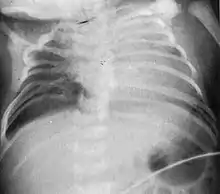

Characteristic radiograph from child with Jarcho-Levin syndrome, spondylocostal dysostosis subtype

In contrast to STD, the subtype spondylocostal dysostosis, or SCD features intrinsic rib anomalies, in addition to vertebral anomalies. Intrinsic rib anomalies include defects such as bifurcation, broadening and fusion that are not directly related to the vertebral anomalies (such as in STD, where extensive posterior rib fusion occurs due to segmentation defects and extreme shortening of the thoracic vertebral column).[6] In both subtypes, the pulmonary restriction may result in pulmonary hypertension, and have other potential cardiac implications.[7]